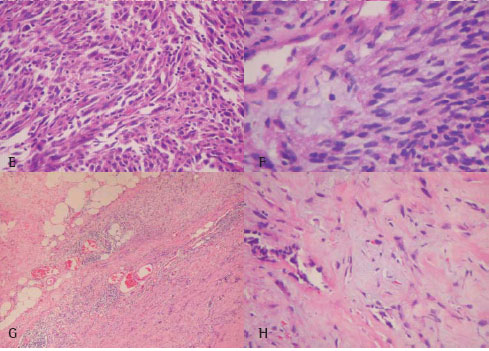

Difficulty in reaching diagnosis was never due to the small amount of tumor tissue available, but resulted from the histological picture itself. In Figure 1 (panel A to F) and Figure 2 (panel A to F) are examples respectively of typical and atypical histologic pattern. Data providing insights into the epidemiology and prognosis were collected from the case histories and by means of interview. The survival time was calculated from the date of diagnosis. Other details about the patients selected for the study are summarized in Table 1.

Immunohistochemistry confirmed 40 cases of mesothelioma and 11 adenocarcinomas but was unable to classify 7 cases of atypical histologic pattern for mesothelioma. Among mesotheliomas cases, twenty four were positive for calretinin, 9 for thrombomodulin, 8 for Leu-M1 and 1 case immunostained for CEA in very small quantity. Adenocarcinoma was considered in 5 out of 12 cases classified as atypical histological pattern for mesothelioma and in 6 out of 46 cases belonged to the typical category. Seven among these 11 cases of adenocarcinomas, 7 were CEA positive, 8 were Leu-M1 positive and 3 were calretinin positive. After exclusion of the adenocarcinomas by immunohistochemistry, subtyping among the mesotheliomas cases found 22 epithelial (Figure 1A, 1B), 12 biphasic (Figures 2C, 2D), 5 sarcomatoid (Figures 3E, 3F) and 1 desmoplastic.